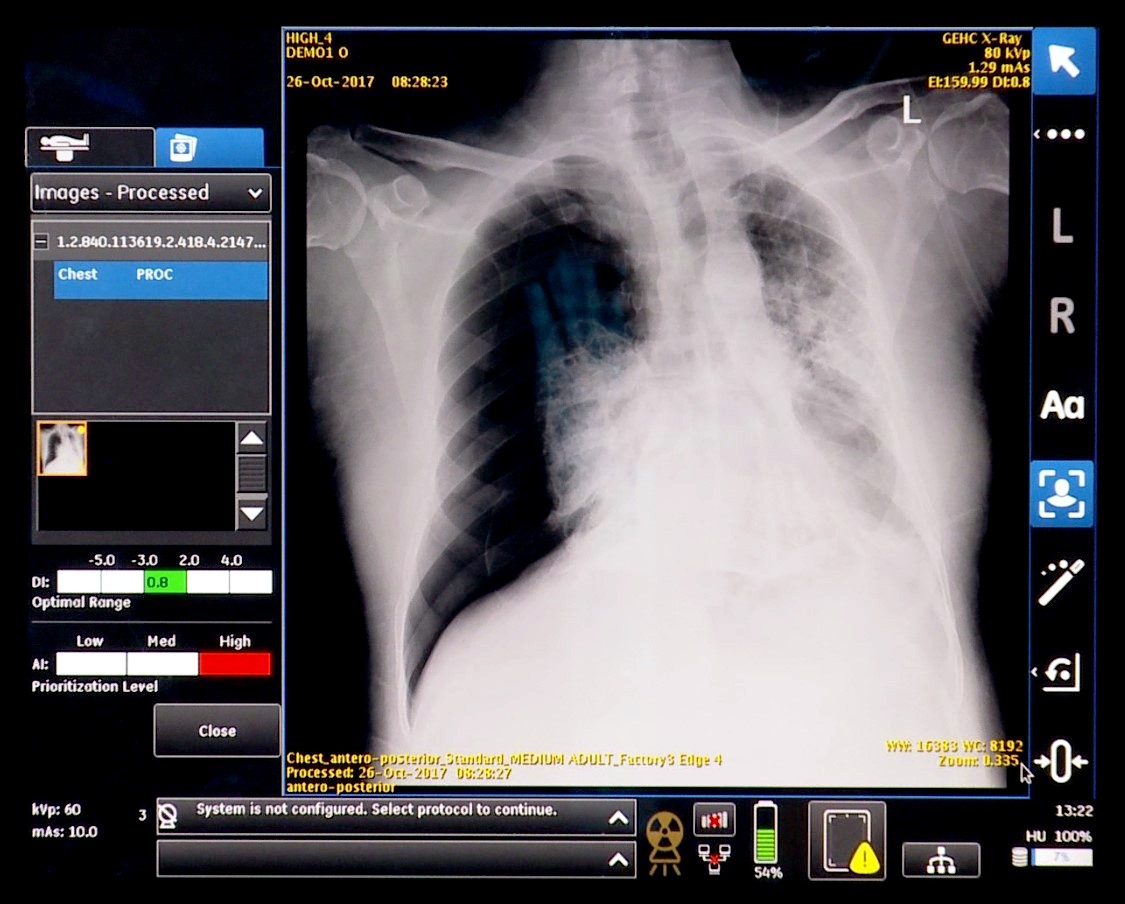

At RSNA 2017, GE showed how integrating a smart algorithm with imaging technology might protect patient and provider. The company demonstrated a work in progress that combined a smart algorithm and a portable X-ray unit. Developed in concert with the University of California in San Francisco, the algorithm is designed to look for signs of pneumothorax (collapsed lung) in the chest radiographs of surgical patients before they exit the operating room.

“There is a huge financial benefit if you don’t have to incur a massive cost because of a collapsed lung,” said Keith Bigelow, general manager of analytics at GE Healthcare. “And, if you catch it before it becomes an emergency, operationally you’re not consuming that room for an emergency procedure.”

The algorithm might be adapted for other purposes, Bigelow noted, for example, to check for proper placement of a chest tube. GE is working on it, he said.